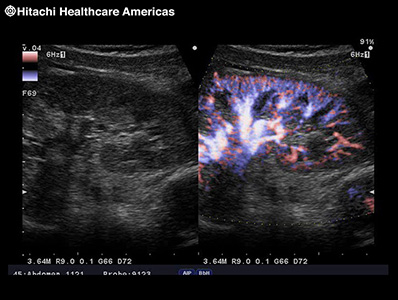

Displays blood flow with directional information at higher frame rates and spatial resolution compared to conventional methods. Detail and accuracy of blood flow information is greatly increased with reduced blooming of color.

Real-time side-by-side display of a B-mode image and Color Doppler image assisting in easy anatomical interpretation of blood flow.